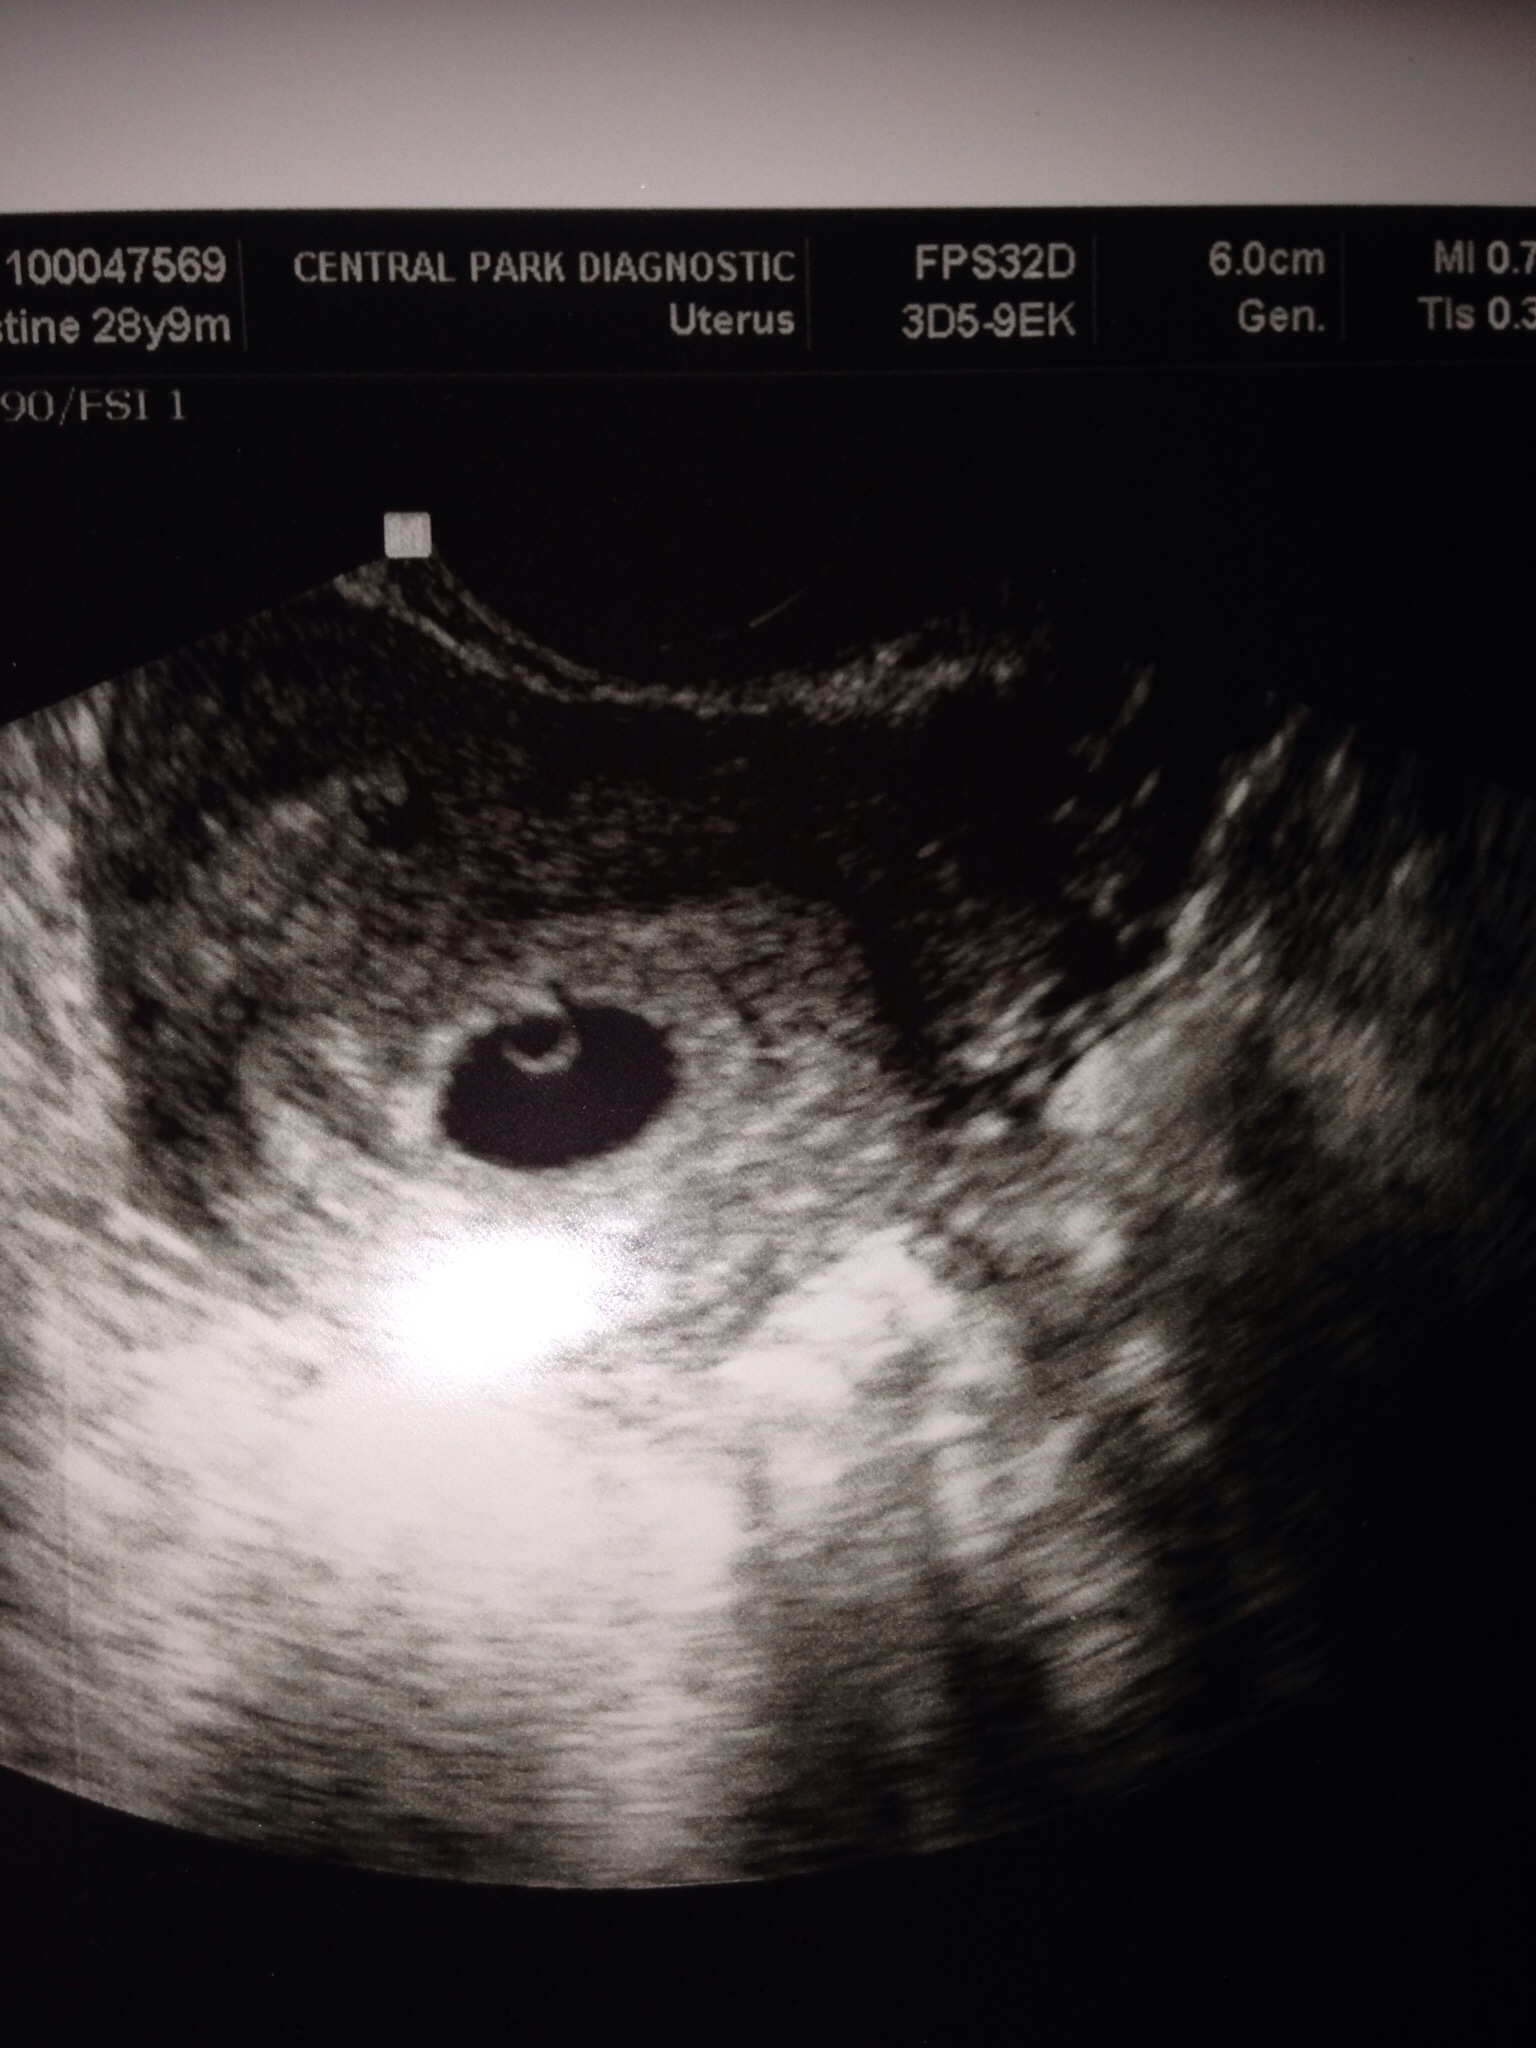

Beginning of July I heard something snap in my ankle and couldn’t walk. Went to the ER and nurse told me they needed to take some XRays but wanted to do a pregnancy test first. I was pregnant! Carl was in the hospital room with me so we got the news at the same time. What a day! Turns out I had gotten pregnant about 2 weeks after Carl proposed 🙂

Baby was healthy and aside from my ankle

I was in good shape – full speed ahead. We are going to be parents!